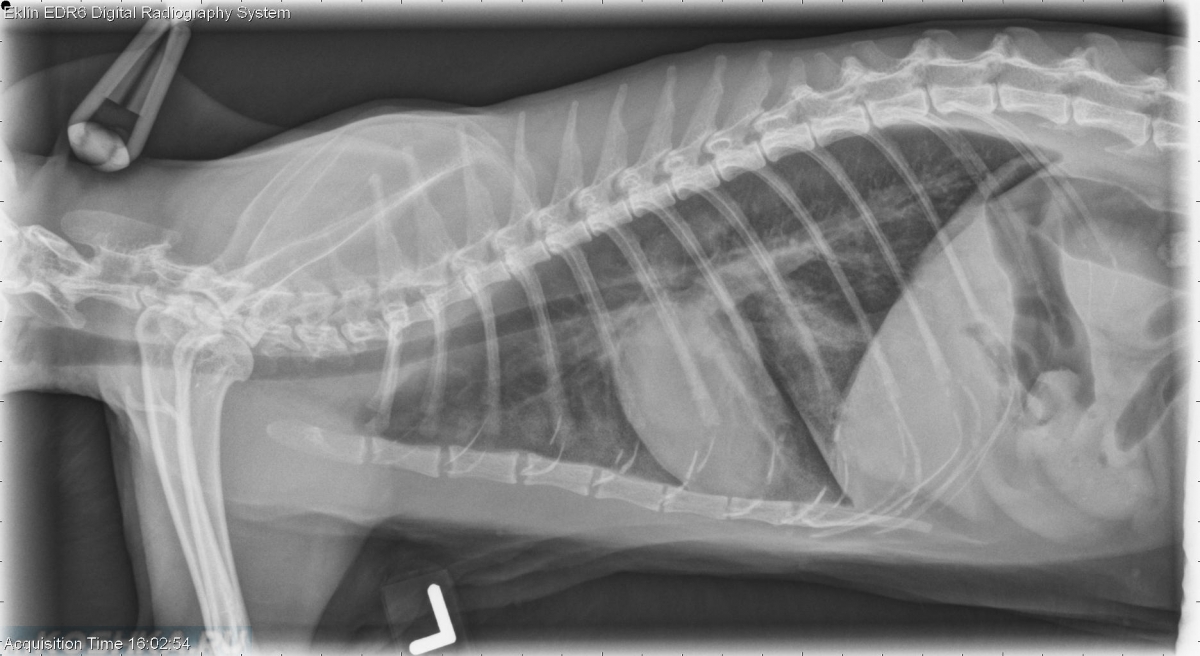

В клинике собаке сделают рентген, который подтвердит или опровергнет отек легких, а также проведут осмотр собаки, прослушают ее и выполнят ряд лабораторных исследований.

Для диагностики отека легких у собак используются такие методы, как аускультация, рентгенография грудной клетки или ультразвуковое исследование, также требуется анализ крови. Электрокардиограмма, анализ мочи и измерение кровяного давления — другие важные тесты, позволяющие выяснить, есть ли у вашей собаки отек легких.

Если состояние вашего питомца стабильное, можно выполнить рентгенографию грудной клетки, положив собаку на спину. На этой рентгенограмме могут быть признаки отека легких, такие как повышенная интерстициальная или альвеолярная непрозрачность. У собак, страдающих кардиогенным отеком легких, также могут наблюдаться кардиомегалия и расширенные легочные вены.

Рентгеновские снимки являются основным инструментом для диагностики отека легких, поскольку они выявляют жидкость внутри легких собаки. Рентген также может выявить увеличенное сердце или другие аномалии сердечной мышцы.